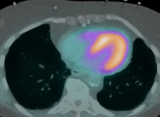

针对患者的计划可以改善放射治疗结果

放射治疗的目标是向肿瘤目标提供规定的辐射剂量,同时限制对周围正常组织的损伤。目前,这是使用基于人群的治疗计划优化来实现的,该优化基于预先定义的基于剂量的目标和风险器官 (OAR) 限制,这些限制是从广泛的患者群体对辐射的聚合反应中发展而来的。不幸的是,这种标准化治疗计划的有效性和毒性各不相同,因为患者及其肿瘤具有个体生物学特征。 2022-10-13 放射诊疗